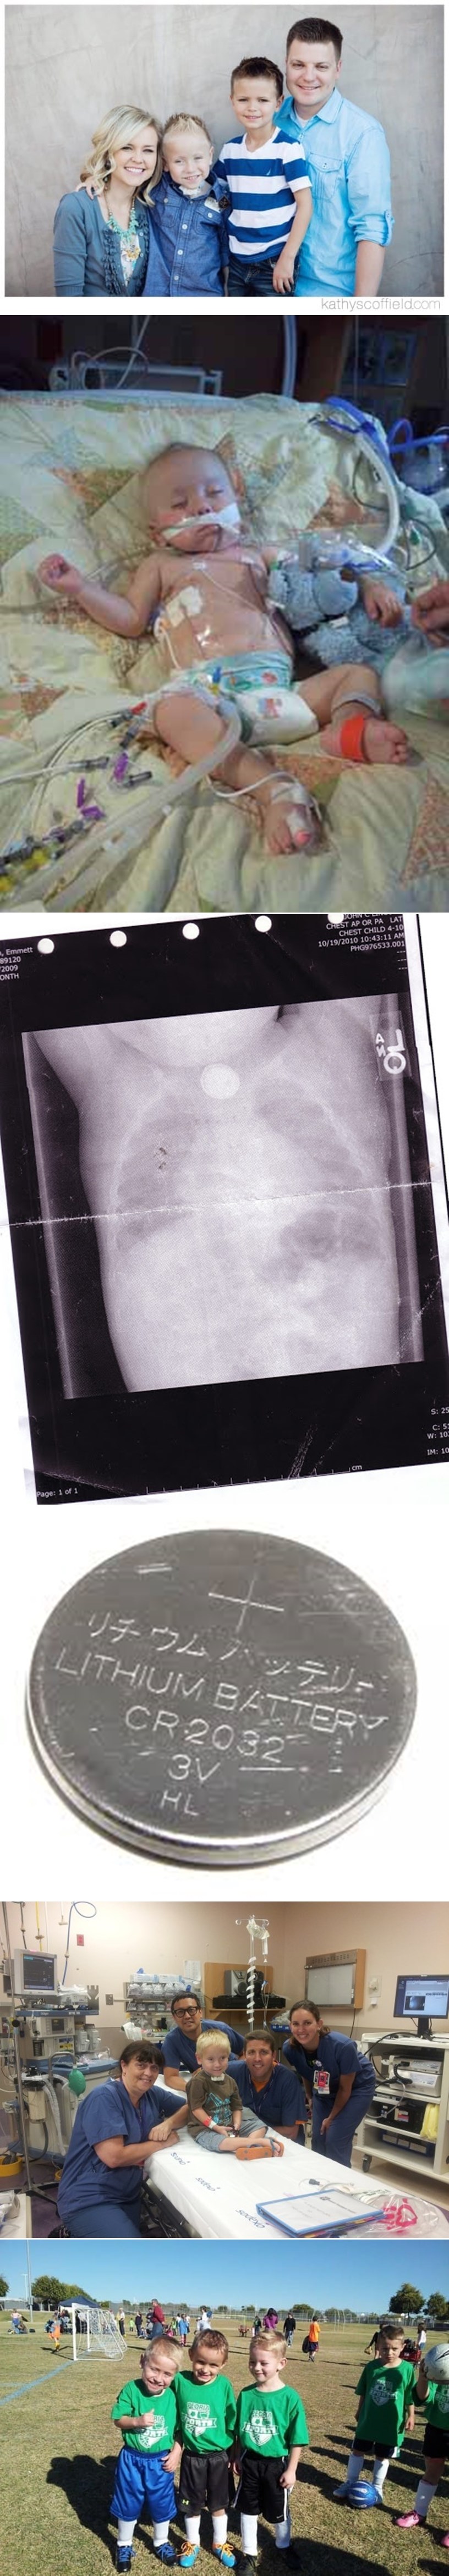

Ova opasnost nikome nije pala na pamet, a teško ju je otkriti na prvi pogled. Kad je maleni Emmett imao samo godinu dana, na podu je pronašao litijsku "gumb-bateriju" koja je slučajno ispala iz stražnjeg kraja kućnog DVD-playera bez da je itko primjetio. Pronašao ju je i, naravno, progutao.

Ipak, shvatili su da se nešto događa kad je dječak postao letargičan, zbunjen, dobio groznicu - pojurili su liječniku, ali on je rekao da je to samo prehlada i poslao ih kući.

Vratili su se kad je počeo iskašljavati krv!

Iako liječnik i dalje nije znao što mu je, ipak je imao toliko pameti da ih pošalje na Hitnu, gdje je na rentgenu otkrivena baterija u želucu. Kiselina iz nje mu je teško oštetila jednjak i probavni trakt.

Srećom, Emmett je od rođenja borac i nekako se izvukao usprkos teškim ozljedama, a kroz posljednje je četiri godine prošao čak 65 operacija. Danas je normalni petogodišnjak koji igra nogomet, normalno jede i igra se, a priča zahvaljujući umjetnim glasnicama. Jednjak mu je morao biti u potpunosti zamijenjen, a problemi su nastali čak i u plućima!

Dječak nije mogao normalno jesti dvije godine i disao je samo zahvaljujući cjevčici. Takva baterija, nakon što je se proguta, krene paliti tkivo u roku od samo dva sata.

Nalaze se svuda, od privjeska za ključeve za daljinsko otključavanje auta, do glazbenih blagdanskih čestitki, daljinskih upravljača, digitalnih vaga, kalkulatora, satova, slušnih aparata, termometara... podijelite ovo s drugim roditeljima, možda nekome spasi život.